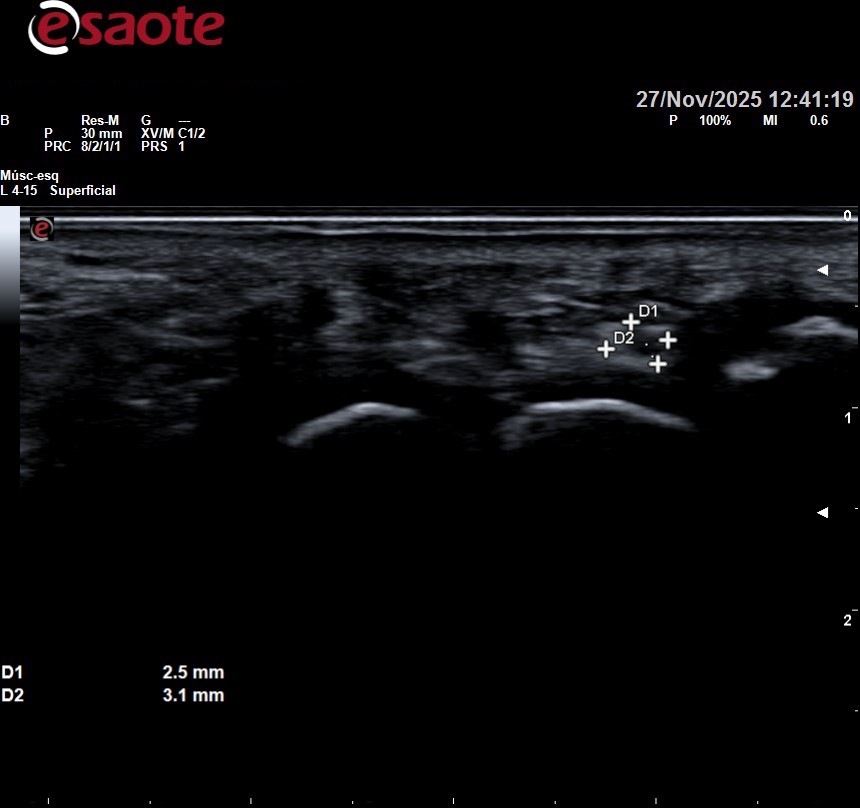

Imagenes ecográficas normales y de un neuroma de morton

Se puede observar arriba la ecografía de una paciente con neuroma de morton entre tercer y cuarto metatarsiano sintomatológico, que posteriormente se infiltró. Se observa como desde lo metatarsianos hacia los dedos el nervio se va haciendo más gordo. En la foto de abajo a la derecha lo vemos a lo largo en esa zona negra circular que se observa de la mitad de la imagen hacia la izquierda.